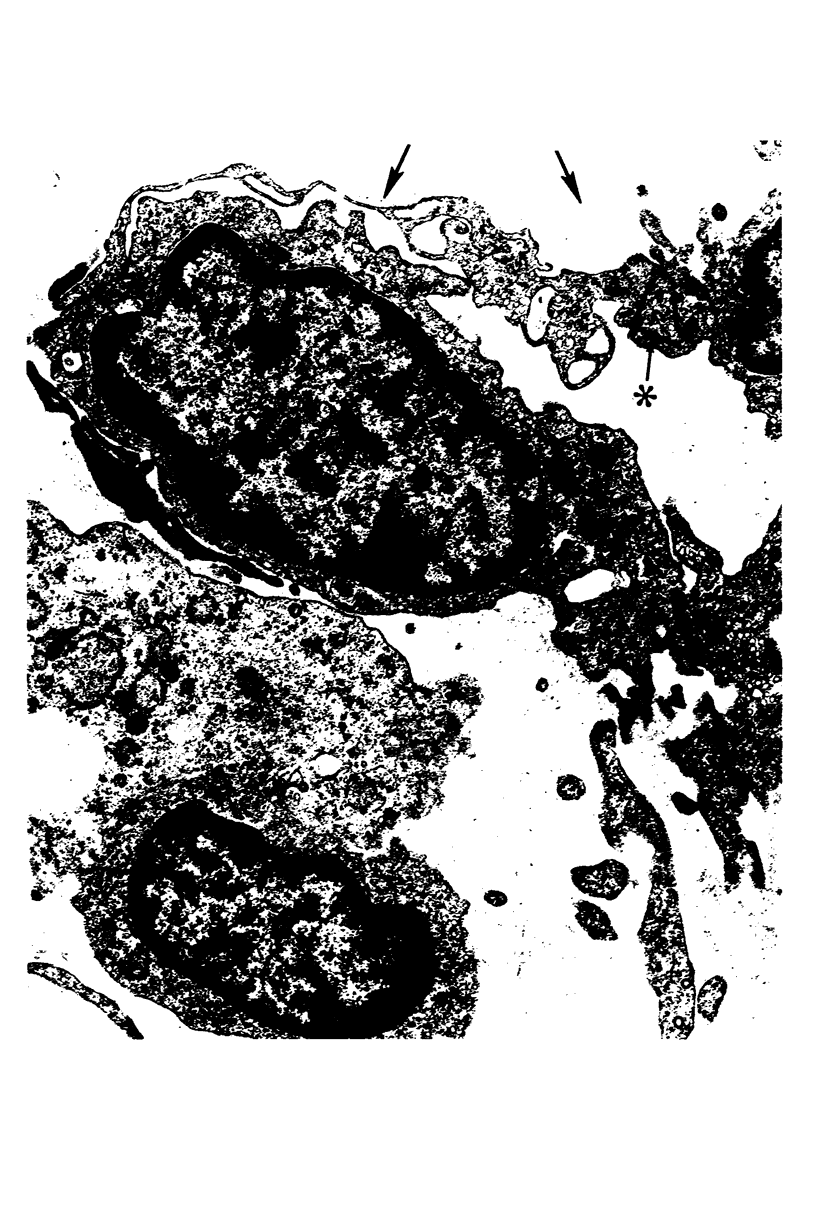

With removal of large numbers of macrophages by airway lavage, Type 1 cells were isolated in heterogeneous cell populations following the stepwise dissociation of lung tissue. Using a carefully timed collagenase-trypsin digestive sequence at 37 C, unwanted cellular and noncellular lung components were minimized prior to selective release of Type 1 cells. Resulting heterogeneous cell suspensions containing well-preserved Type 1 cells, as determined by electron microscopy, were layered onto a shallow gradient (3 to 6% Ficoll in minimal essential medium [MEM]) and separated at unit gravity into enriched subpopulations of various cell types. These included various fractions enriched with respect to Type 1 cells (70%), Type 2 cells (82%), and macrophages (81%). Identification of Type 1 cells following their isolation and gradient enrichment was established by light microscopic staining techniques and by specific cell surface characteristics in vitro as visualized by electron microscopy.

- Rosenbaum R. M., Picciano P. The type 1 alveolar lining cells of the mammalian lung. II. In vitro identification via the cell surface and ultrastructure of isolated cells from adult rabbit lung. Am J Pathol. 1978 Jan;90(1):123–144. [PMC free article] [PubMed] [Google Scholar]